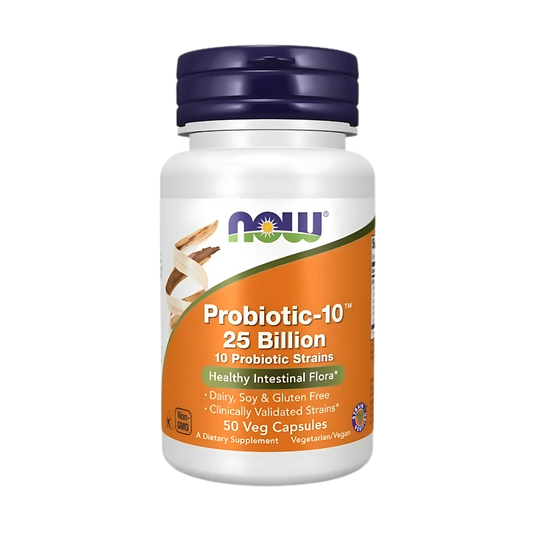

Now Probiotic-10 25 Billion 10 Probiotic Strains 50 Veg Caps

Regular price Tk 2,950.00 BDTRegular priceUnit price / perTk 3,450.00 BDTSale price Tk 2,950.00 BDTSold out -